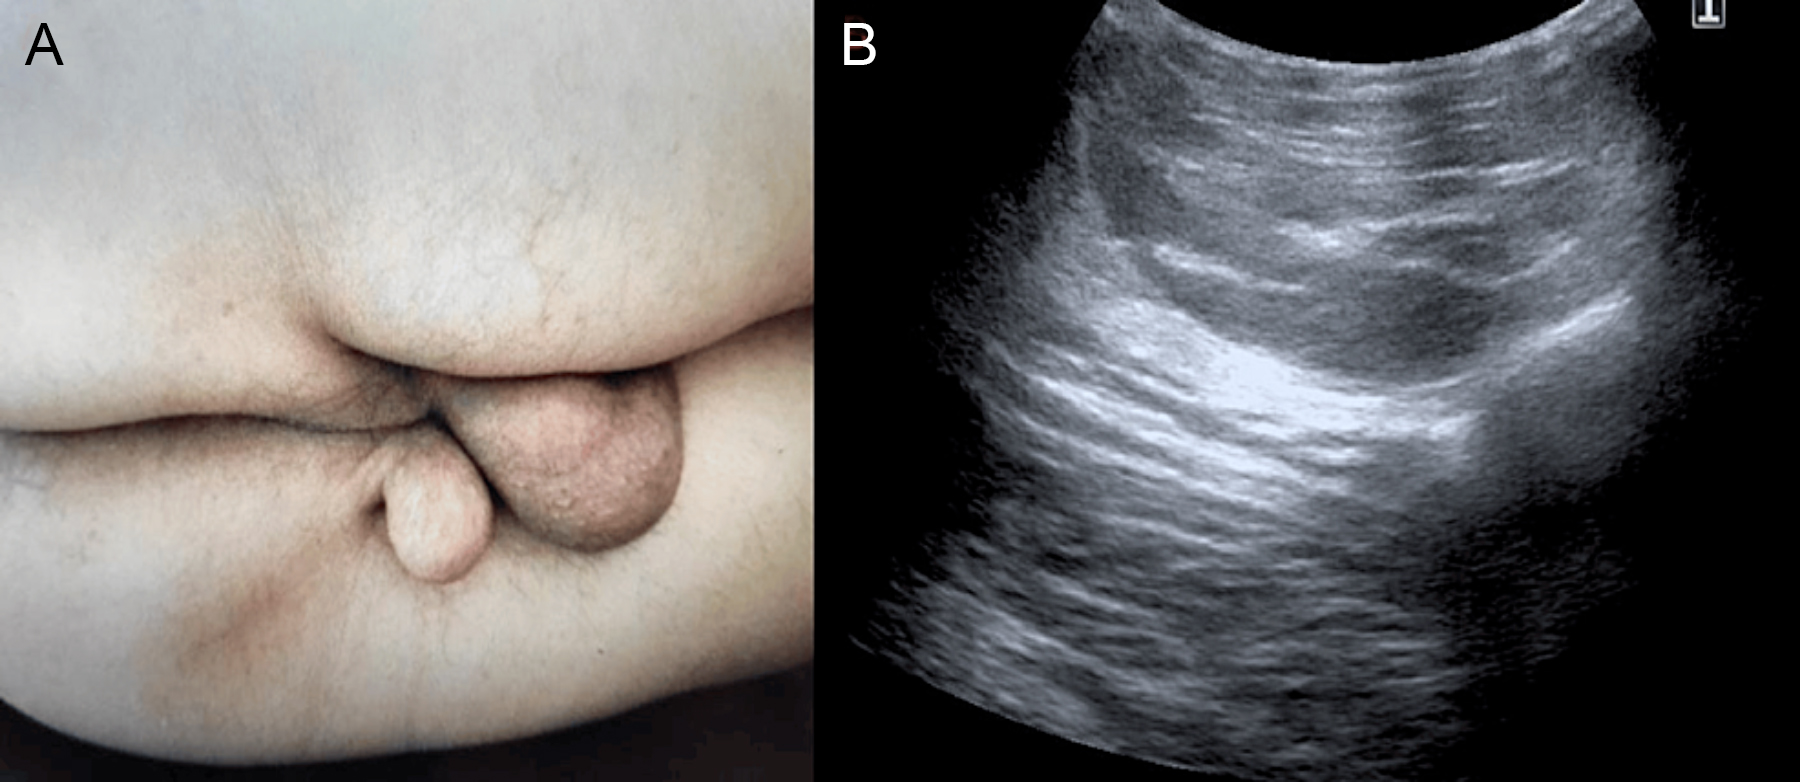

On physical examination, a soft accessory scrotal mass was palpated in the perineal region just caudal to the scrotum. The mass was unrelated to the testes and showed a wrinkled skin area and some hair in the centre. On USG, a 4 × 3 cm mass with adipose tissue echogenicity was evaluated in the favour of lipoma. The histological diagnosis revealed a lipoma with accessory scrotum (Figure 2).

Figure 2: Presentation of an accessory scrotum associated with a perineal lipoma in a 62-year. (A) Soft accessory scrotal mass. (B) Ultrasonography image of the scrotal mass.